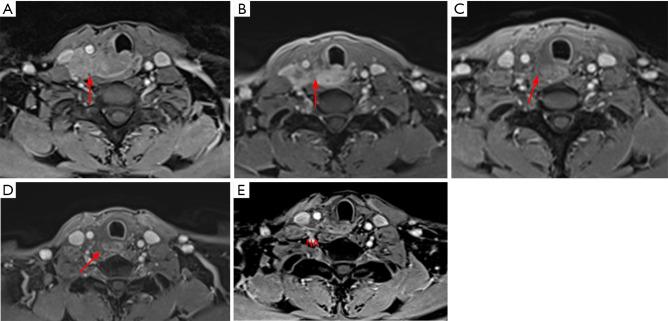

Intrathyroidal thymic carcinoma (ITC) is an extremely rare type of thyroid cancer with very limited knowledge of its clinical characteristics and optimal treatment modalities. We aimed to assemble the largest ITC cohort to date for a better understanding.

A total of 43 cases with ITC were included. Eighteen patients (41.9%) had cervical or mediastinal lymph node metastases, while 16 (37.2%) had distant metastasis at presentation. Ten patients with locally advanced disease received palliative resection and following adjuvant radiotherapy, but none of them showed local progression. After a median follow-up of 69 months, we observed a favorable prognosis with a 3- and 5-year progression-free survival (PFS) of 92.1% and 59.8%, and a 3- and 5-year disease-specific survival (DSS) of 97.0% and 93.1%, respectively. Multivariate analysis showed that palliative resection (HR =5.68, 95% CI: 1.48-21.76, P=0.01) and lateral lymph node metastasis (HR =12.27, 95% CI: 2.40-62.81, P=0.003) were independent risk factors of tumor progression. Partial response was achieved in two patients who received immunotherapy combined with targeted therapy or chemotherapy.

Despite with an overall favorable survival, ITC is still prone to lymph node and distant metastasis. Lateral neck metastasis and incomplete tumor resection predicted a poorer outcome. Once achievable, radical surgery combined with radiotherapy should be performed to improve local control, while immunotherapy and targeted therapies are potentially effective in advanced disease.